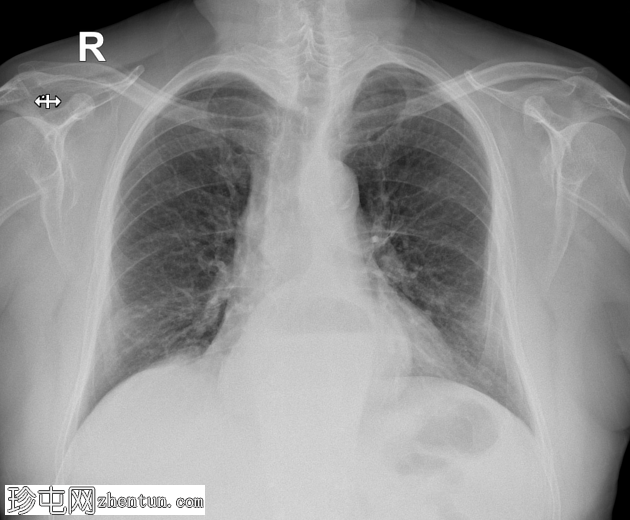

裂孔疝

边界清晰的卵圆形心后阴影,伴有气液平。野大体正常。双侧未见胸腔积液。

鉴于心后气液平及肠管缺失,这些发现提示食管裂孔疝,最有可能是滑动型。

胸部X光检查中,食管裂孔疝通常表现为后纵隔内边界清晰的心后气液平,最常发生在左侧。膈肌轮廓可能隆起或模糊。钡餐检查是确诊的最佳方法,钡餐检查可显示膈肌上方的胃疝和胃食管连接处。